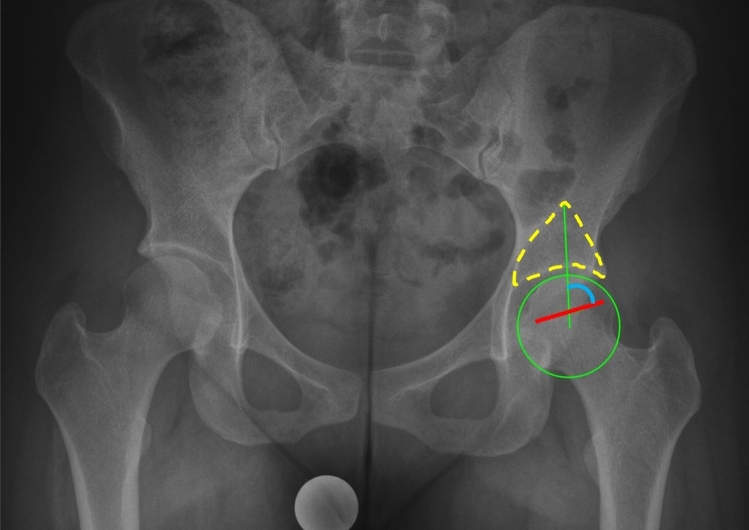

The GAA (Fig. 1) was measured on standing a.p. pelvic radiographs meeting the criteria to be regarded as neutrally rotated and tilted: three cm between the tip of the coccyx and the superior aspect of the symphysis pubis and symmetric obturator foramen21,22. An angle between two lines was measured (Fig. 1, blue semicircle). The first line (Fig. 1, green line) extends between the rotational center of the hips, which is determined by a best-fit circle around the femoral head, and the tip of the gothic arch (Fig. 1, yellow dotted-line). The base of the Gothic arch is formed by the sourcil, while the trabeculae forming the lateral aspect of the arch extend from the lateral acetabular rim toward the sacroiliac joint, while the medial aspect of the arch forms an arc of dense cancellous bone extending from the quadrilateral plate towards the anterior superior and anterior inferior iliac spines. The second line corresponds to the scar of the physeal growth plate, identical to the reference in the FEAR index15 (Fig. 1, red line). The central third of the scar is a straight line connecting its medial and lateral ends.

Figure 1.

To measure the Gothic Arch Angle (blue semicircle), an angle between two lines is measured: The first line (green) extends between the center of the femoral head, which is determined by a best-fit circle around the femoral head (green circle), and the peak of the gothic arch (yellow dashed line). The second line (red) corresponds to the middle third of the physeal scar.